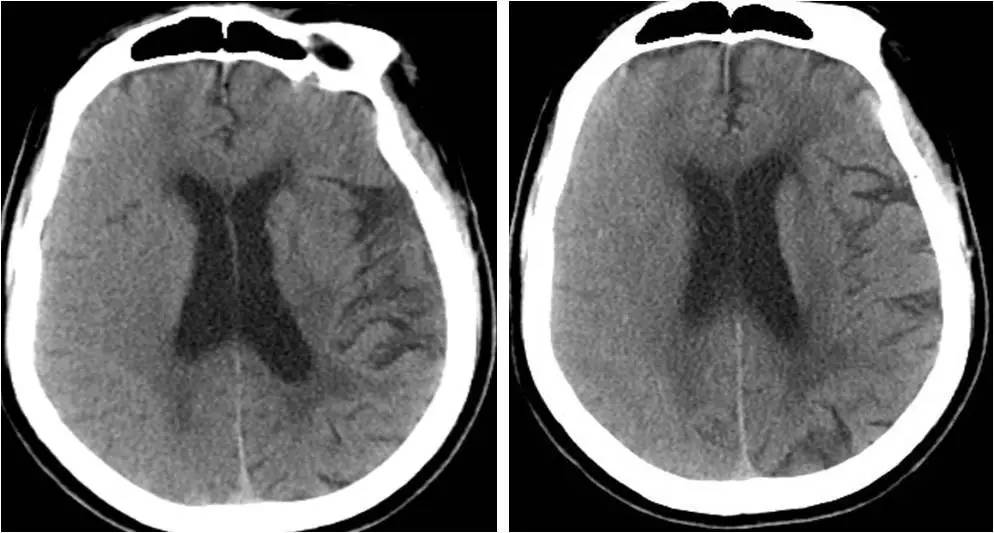

》术后6小时,出现左侧肢体无力,无头痛,无恶心、呕吐;

》查体:嗜睡状态,双眼向右凝视,左上肢肌力0级,左下肢肌力Ⅲ级,肌张力稍低,感觉正常,病理征阴性;

》心电监护示:心率 82次/分,血压 120/60mmHg,血氧饱和度 97%。

复查DSA,右侧颈内动脉起始部支架定位良好,支架内血流通畅,右侧大脑中动脉显影无异常。

不同时间CT表现